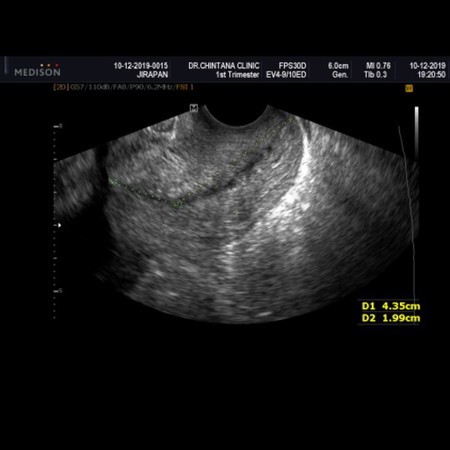

ความยาวปากมดลูก

วันนี้ไปตรวจวัดปากมดลูกมา หมดกังวลค่ะ ปากมดลูกยาว 6 ซม. อายุครรภ์ 18 สัปดาห์ 3 วัน